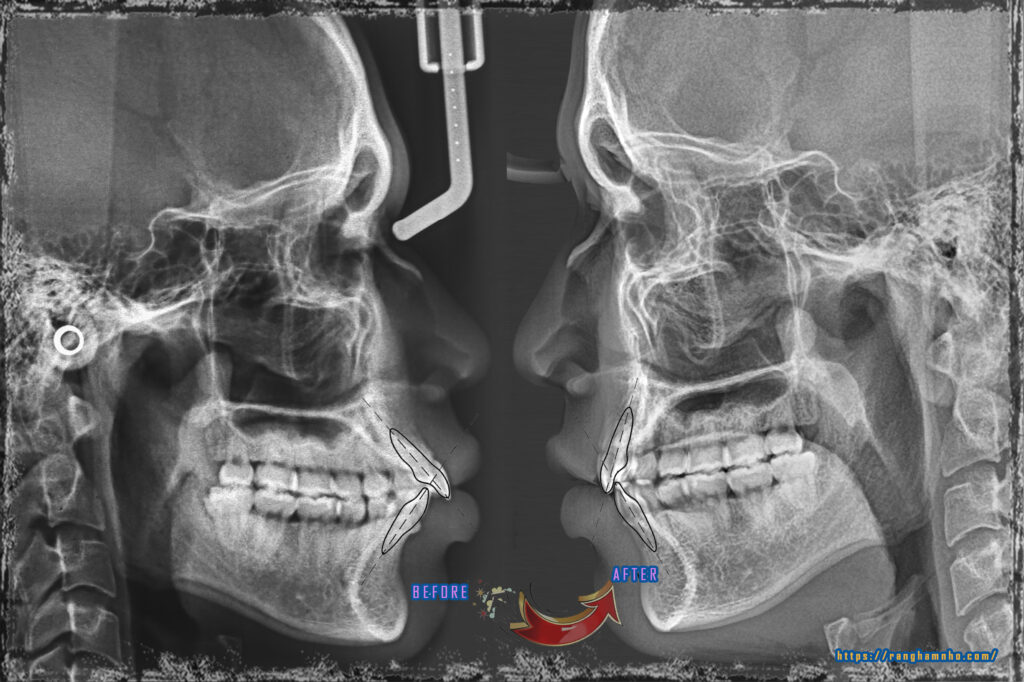

Hình ảnh so sánh trước niềng và sau niềng

BN nam sinh năm 1995 khớp cắn hạng II răng chen chúc, góc liên răng cửa gần như vuông. BN đã được nhổ 4R4, đang trong quá trình đóng khoảng nhưng phát sinh hiệu ứng cuộn không mong muốn do xương “rắn”…v.v..